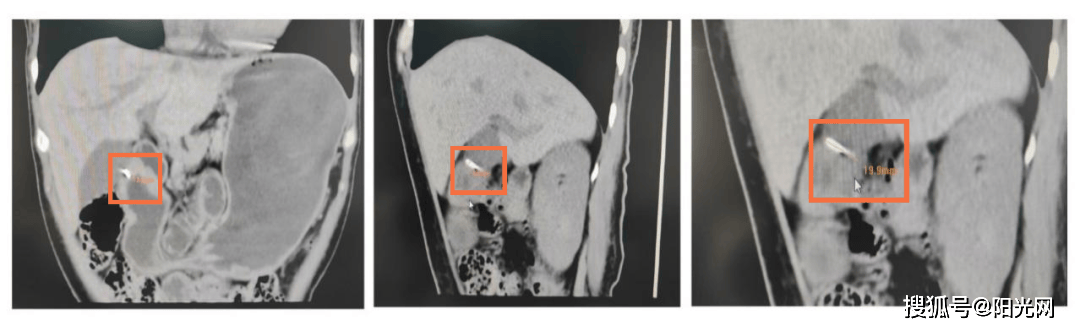

这会是问题的起点吗?医生立即为她安排了更精细的128排螺旋CT检查,并进行了三维重建。

CT发现体内金属异物

这次,谜底终于露出了蛛丝马迹。影像显示,她的胃壁内可见一个细长的条状高密度影。这个影子非常隐蔽,在普通检查中很容易被忽略。结合她最初咽喉刺痛的经历,医生们判断:这很可能是一个被胃壁完全包裹的异物。就像“潜水艇”潜入了深海,它藏在胃壁肌肉里,导致多次胃镜观察胃内表面都“风平浪静”,无法发现。